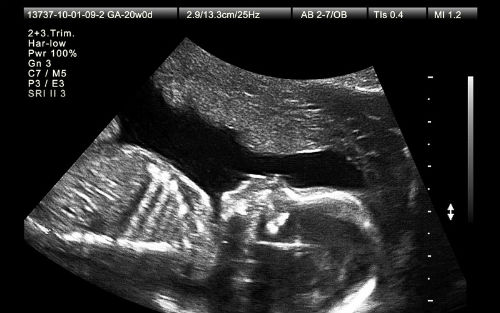

超声波往往被用于产前筛查。怀孕妇女可以选择的几种产前筛查中,这只是其中一种。

在羊膜腔穿刺术中,一根针通过孕妇的腹部刺入羊膜腔。羊水样本被抽取出来,用于筛查唐氏综合症之类的基因异常。